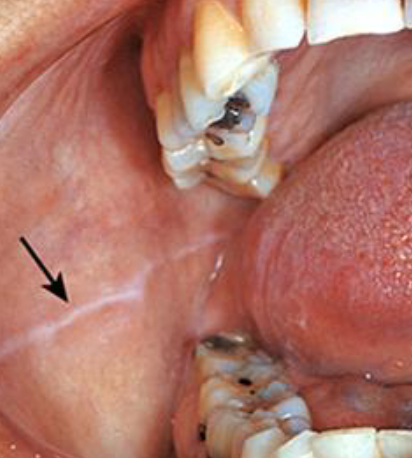

leukoedema

generalized gray-white film, common in AFRICAN AMERICAN individuals, becomes less prominent when mucosa is stretched